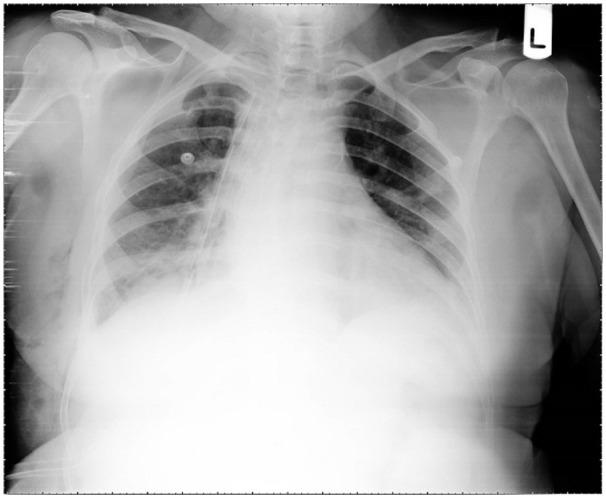

The adult Bochdalek hernia is one of the right-sided diaphragmatic hernias that less than 30 cases reported until now. Here, we report a 64-year-old female patient who presented with dyspnea, abdominal pain, and nausea. Primary imaging showed a right-sided diaphragmatic hernia that contained the liver and right colon. At first, the patient underwent a right posterior thoracotomy, and the diaphragmatic defect was repaired. After 2 days, abdominal peritonitis happened then a midline laparotomy was performed. Finally, it was clear that the main problem was the obstructed and perforated descending colon mass that was presented with Bockdalek hernia. Unfortunately, the patient passed away 2 days after the operation. It should be considered that an increase in intra-abdominal pressure like the presence of obstructed colon mass can cause this rare hernia and It is important to determine the reason for the presentation of the symptomatic Bochdalek hernia in adult patients.

成人博赫达勒克疝是右侧膈疝之一,迄今为止报道的病例不足30例。在此,我们报告一名64岁女性患者,她出现呼吸困难、腹痛和恶心症状。初步影像学检查显示右侧膈疝,疝内容物为肝脏和右结肠。起初,患者接受了右后外侧开胸手术,修复了膈肌缺损。术后2天,发生了腹部腹膜炎,随后进行了正中剖腹手术。最终明确主要问题是伴有博赫达勒克疝出现的降结肠肿块梗阻并穿孔。不幸的是,患者术后2天死亡。应考虑到像结肠肿块梗阻这样的腹内压升高可导致这种罕见疝,确定成人患者出现有症状的博赫达勒克疝的原因很重要。